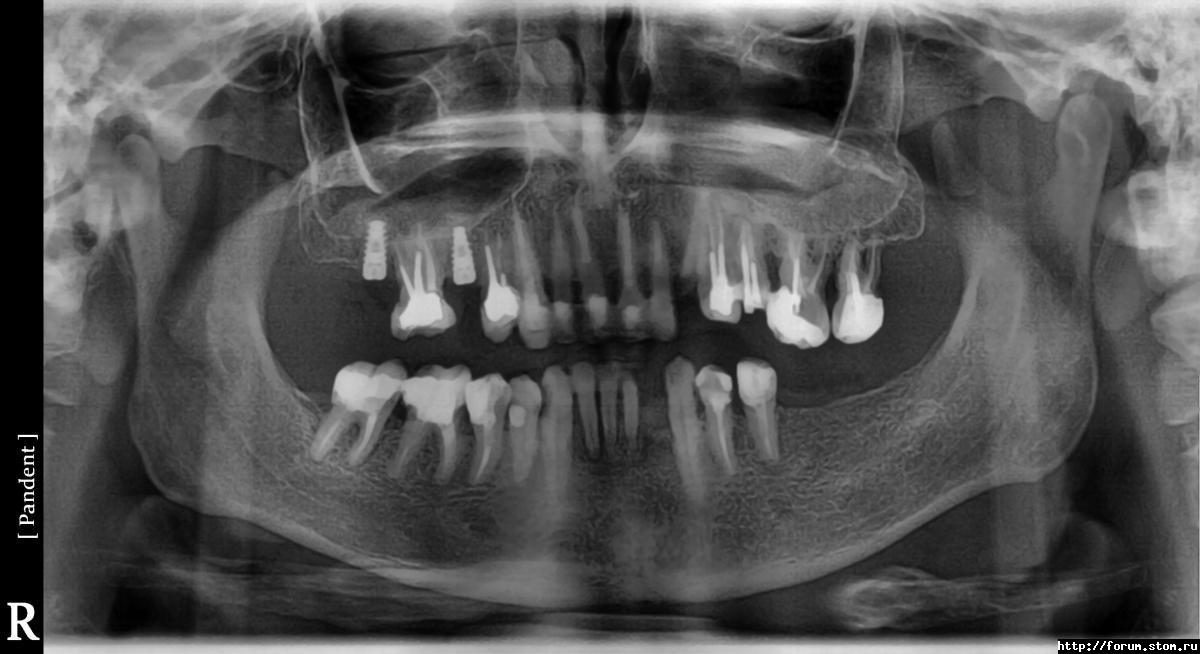

alexy78rus Опубликовано 7 ноября, 2011 Автор Поделиться Опубликовано 7 ноября, 2011 Вот, pls, посмотрите Какую программу лечения можно считать оптимальной. Ссылка на комментарий

Salma Опубликовано 1 ноября, 2011 Поделиться Опубликовано 1 ноября, 2011 Добрый день, Очень обидно, отломался верхний клык, по самую десну.В клиннике, куда я обратился предлагают одномоментное удаление с имплантацией и подсадкой костной ткани. Если шанс сохранить корень?У меня уже поставили два импланта и надо ставить еще 7 штук.Если да - кто в Питере возмется за такую работуБез рентгеновского снимка и желательно фотографии корня в полости рта сказать что либо невозможно Ссылка на комментарий